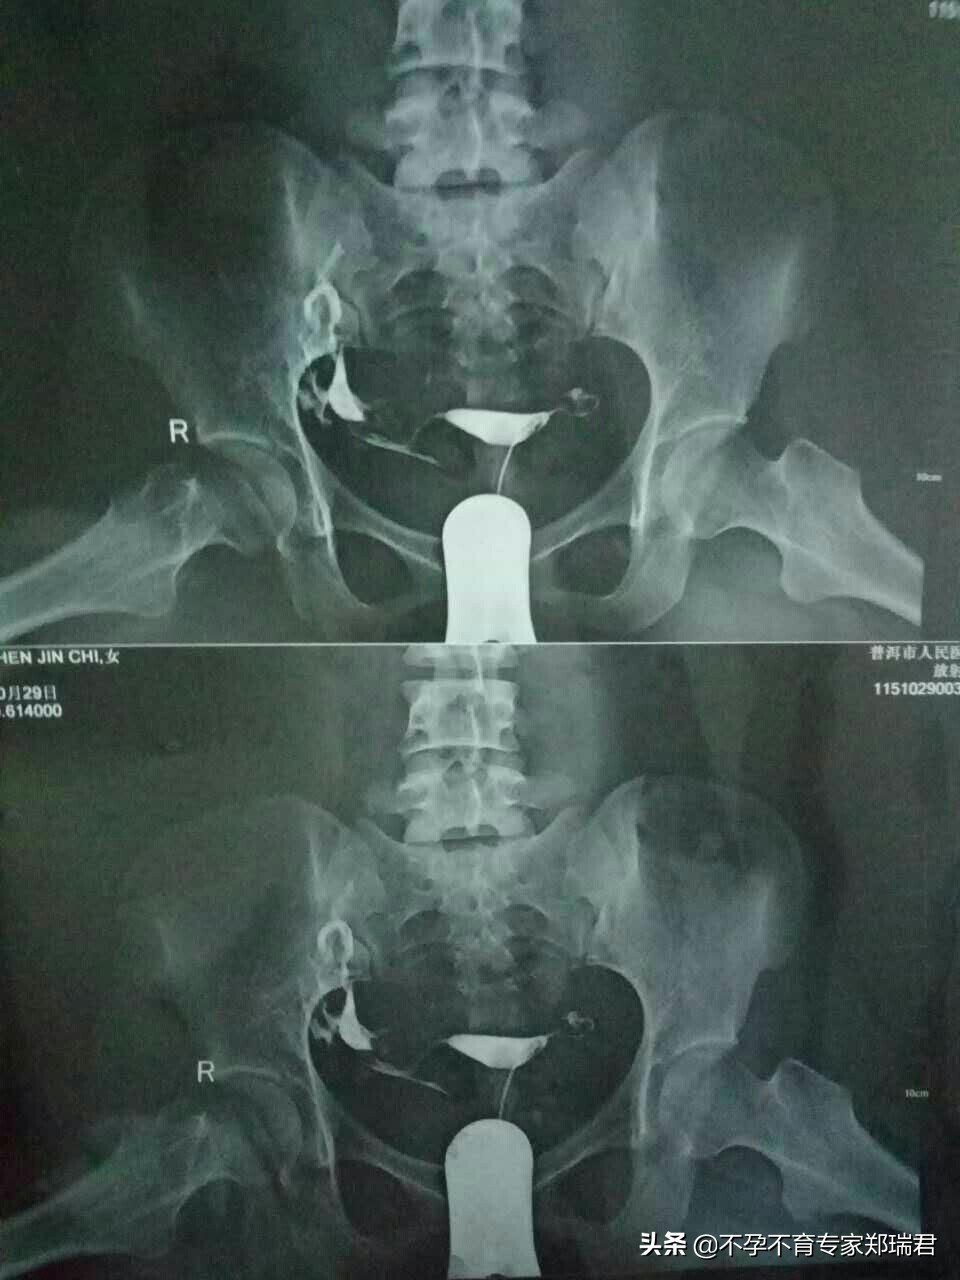

第三周复查的时候,盆腔炎已经全部好了,郑主任说,现在开始治好了炎症,可以开始调输卵管。做了造影检查,发现我是双侧输卵管间质部梗阻。